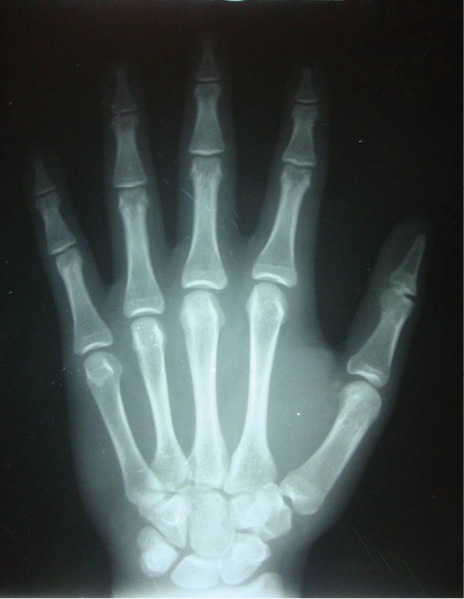

En el estudio imagenológico se observó en la radiografía de tórax, hipoplasia clavicular bilateral y tórax en forma de campana (Figura 2), en la radiografía panorámica se mostró la presencia de once dientes supernumerarios en el maxilar y nueve en la mandíbula (Figura 3), en la radiografía lateral cráneo se observó presencia de huesos wormianos landoideos (Figura 4); en la radiografía carpal se observó longitud simétrica de las falanges y sin alteraciones (Figura 5), de acuerdo con los hallazgos encontrados en el examen físico y la evaluación radiológica, se realizó la impresión diagnóstica de displasia cleidocraneal.

Figura 5. Radiografía carpal sin alteraciones.Fuente: autores.